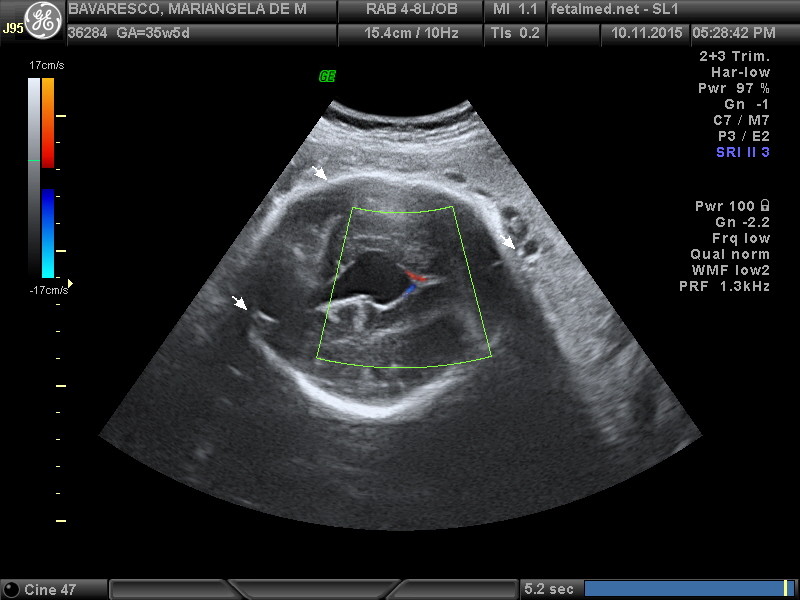

Vídeo cortesia do Dr. Jader Cruz – The Fetal Medicine Foundation

Cisto de Aracnóide

É um saco de líquido na membrana aracnóide que cobre o cérebro e a medula espinal. Há três membranas que cobrem as partes do Sistema Nervoso Central (SNC): a dura-máter, a aracnoide e a pia-máter. Os cistos aracnoides aparecem na membrana aracnoide (espaço subaracnoide). Os lugares mais comuns dos cistos aracnoides intracraniais são na fossa média (perto do lobo temporal), na região supracellar (perto do terceiro ventrículo) e na fossa posterior, onde tem o cerebelo, o ponte, e a medula oblonga.